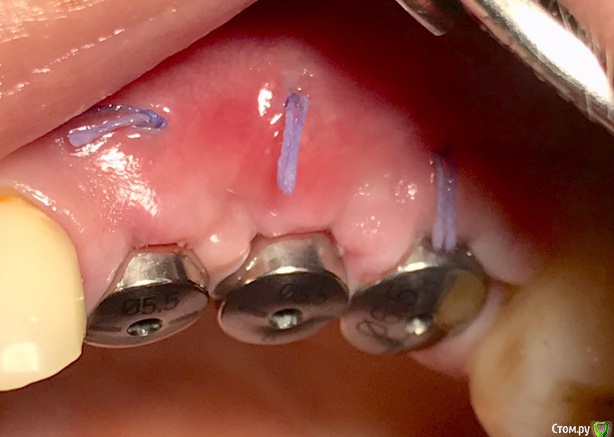

колесников Опубликовано 27 сентября, 2019 Автор Поделиться Опубликовано 27 сентября, 2019 Улучшение объема и качества мягких тканей в пришеечной области у ранее поставленных имплантов ,посредством тоннельной костной пластики. Объём 0,5г. Вид через 6 мес. 3 Ссылка на комментарий